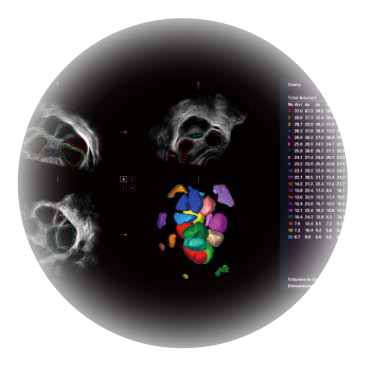

卵泡结构的自动识别和测量,可显示多组测量数据。

大角度腔内容积探头,可完整包络子宫及盆底结构,充分展示组织结构毗邻关系。